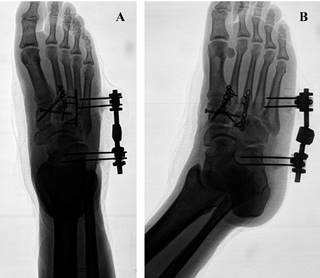

En pacientes con lesiones de alta energía del mediopié: fracturas/luxaciones y significativo daño de tejidos blandos, el protocolo de manejo por etapas incluye la fijación externa. Ésta permite recuperar la longitud y alineación de las columnas óseas favoreciendo la recuperación de las partes blandas, antes de realizar la fijación interna definitiva (Figuras 5 y 6).55,56